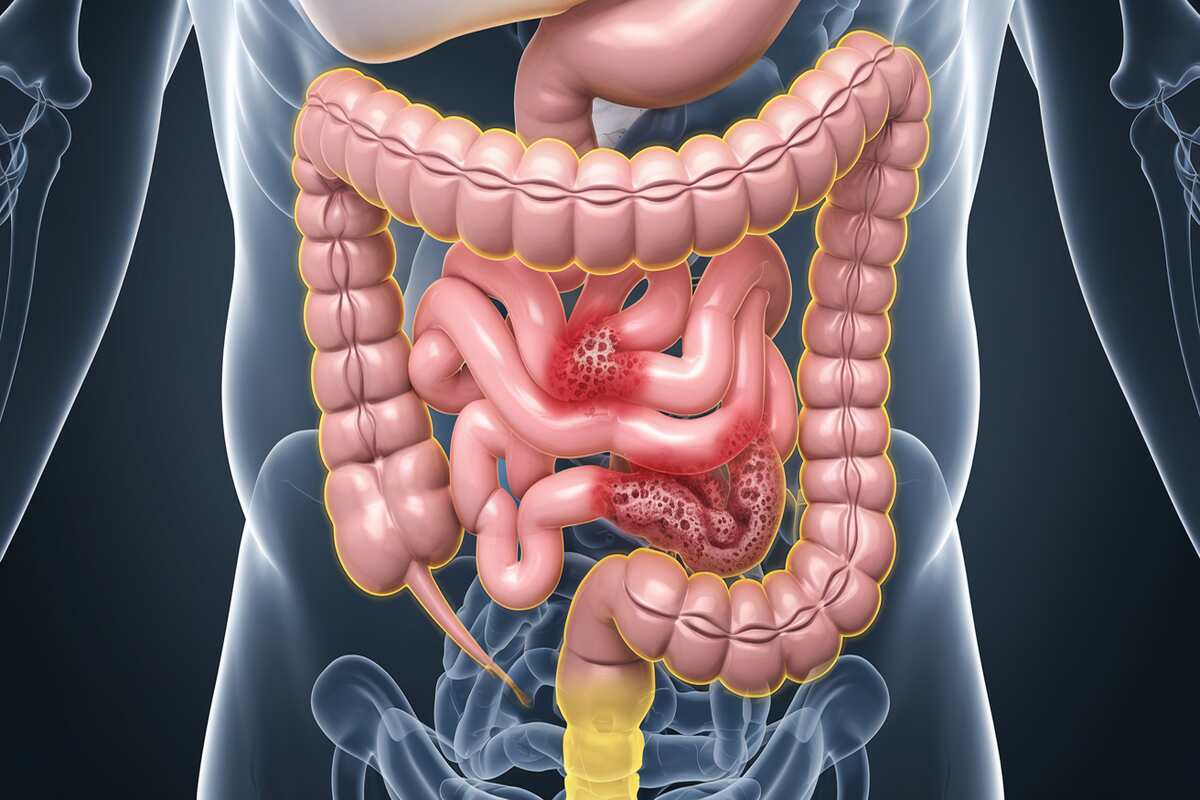

Gastrointestinal Cancers

Gastrointestinal cancers affect the digestive tract, including the stomach, small intestine, and pancreas. They can vary in type and aggressiveness. Chronic inflammatory diseases, including Crohn’s disease, smoking, and a diet heavy in processed foods are risk factors. Symptoms can be vague, often leading to late-stage diagnosis. Early detection through routine tests and symptom awareness are essential for a treatment to be effective.

Gastrointestinal cancers: understanding risks, symptoms, and treatment options for digestive health.

Gastrointestinal cancers: understanding risks, symptoms, and treatment options for digestive health.

Symptoms

- Digestive Issues: Persistent nausea, vomiting, and abdominal pain.

- Unexplained Weight Loss: Significant weight loss without a clear cause can be a symptom.

Prevention

- Healthy Diet: For a nutritious diet, eat a balanced meal rich in fruits, vegetables, and whole grains.

- Avoid Smoking and Excess Alcohol: Reducing these risk factors can lower your chances of developing gastrointestinal cancers.

Treatment

- Surgery: To remove tumors or affected sections of the digestive tract.

- Chemotherapy and Radiation Therapy: Used to target cancer cells and manage symptoms.